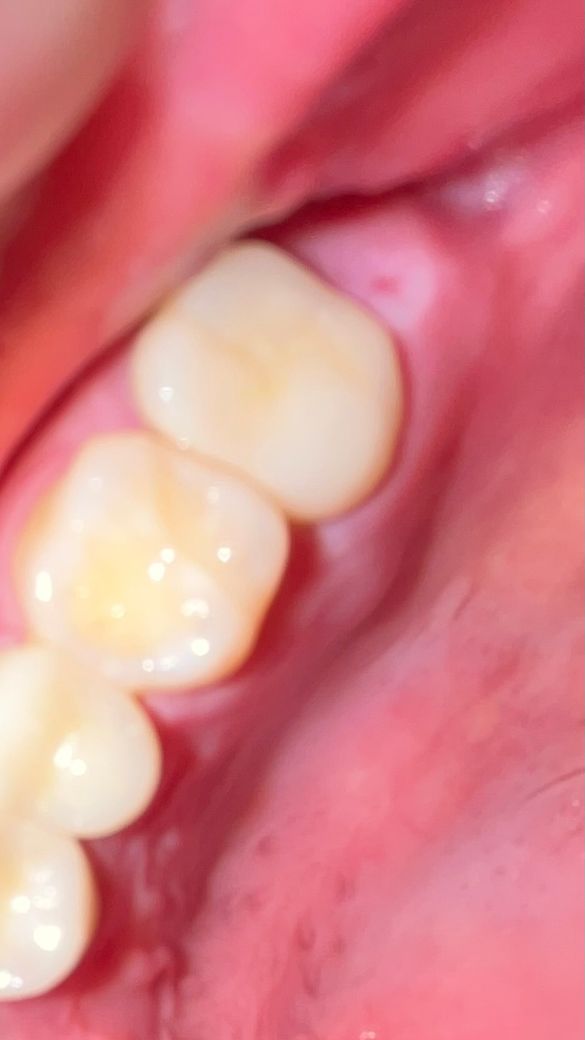

나머지 사진 3장이 방금 찍은 지금 상태입니다.

사진에 보이는 제일 안쪽 어금니를 신경치료 후에 금니로 씌웠었고 몇 년 후 염증이 생겨서 재신경치료를 했습니다. 후에 금말고 레진(정확하게 모르겠어요ㅜ)으로 씌워서 잘 지내다가 올해 2월 초에 그 앞앞 치아 충치때문에 통증이 있어서 해당 치아도 신경치료를 했습니다. 그 사이에 있는 치아도 벽이 썩어서 레진으로 떼웠고요. 치료 후에 원래 있던 통증도 사라지고 아픈 곳도 없었는데 3월 말부터 조금씩 뭔가 만져지면서 아프기 시작해서 4월 1일에 병원에 방문했습니다. 병원에서는 감기 때문일 수 있다며 염증약을 처방해줬고, 3일간 약을 먹었지만 낫지 않았습니다. 그 주 주말에 바로 코감기가 걸려서 잇몸 통증은 잊게 되었는데 어제부터 혀로 만져보니 그 전만큼 아픈 건 아니지만 혀나 손가락으로 눌러보면 분명히 통증이 있습니다. 모양도 더 부었구요..

사진 상으로는 최후방 잇몸에 생긴 염증으로 앞에 치아들과는 연관이 없어 보이지만 통증 부위가 커지고 통증이 증가하면 치과 방문하여 검사 해보는 것이 좋습니다